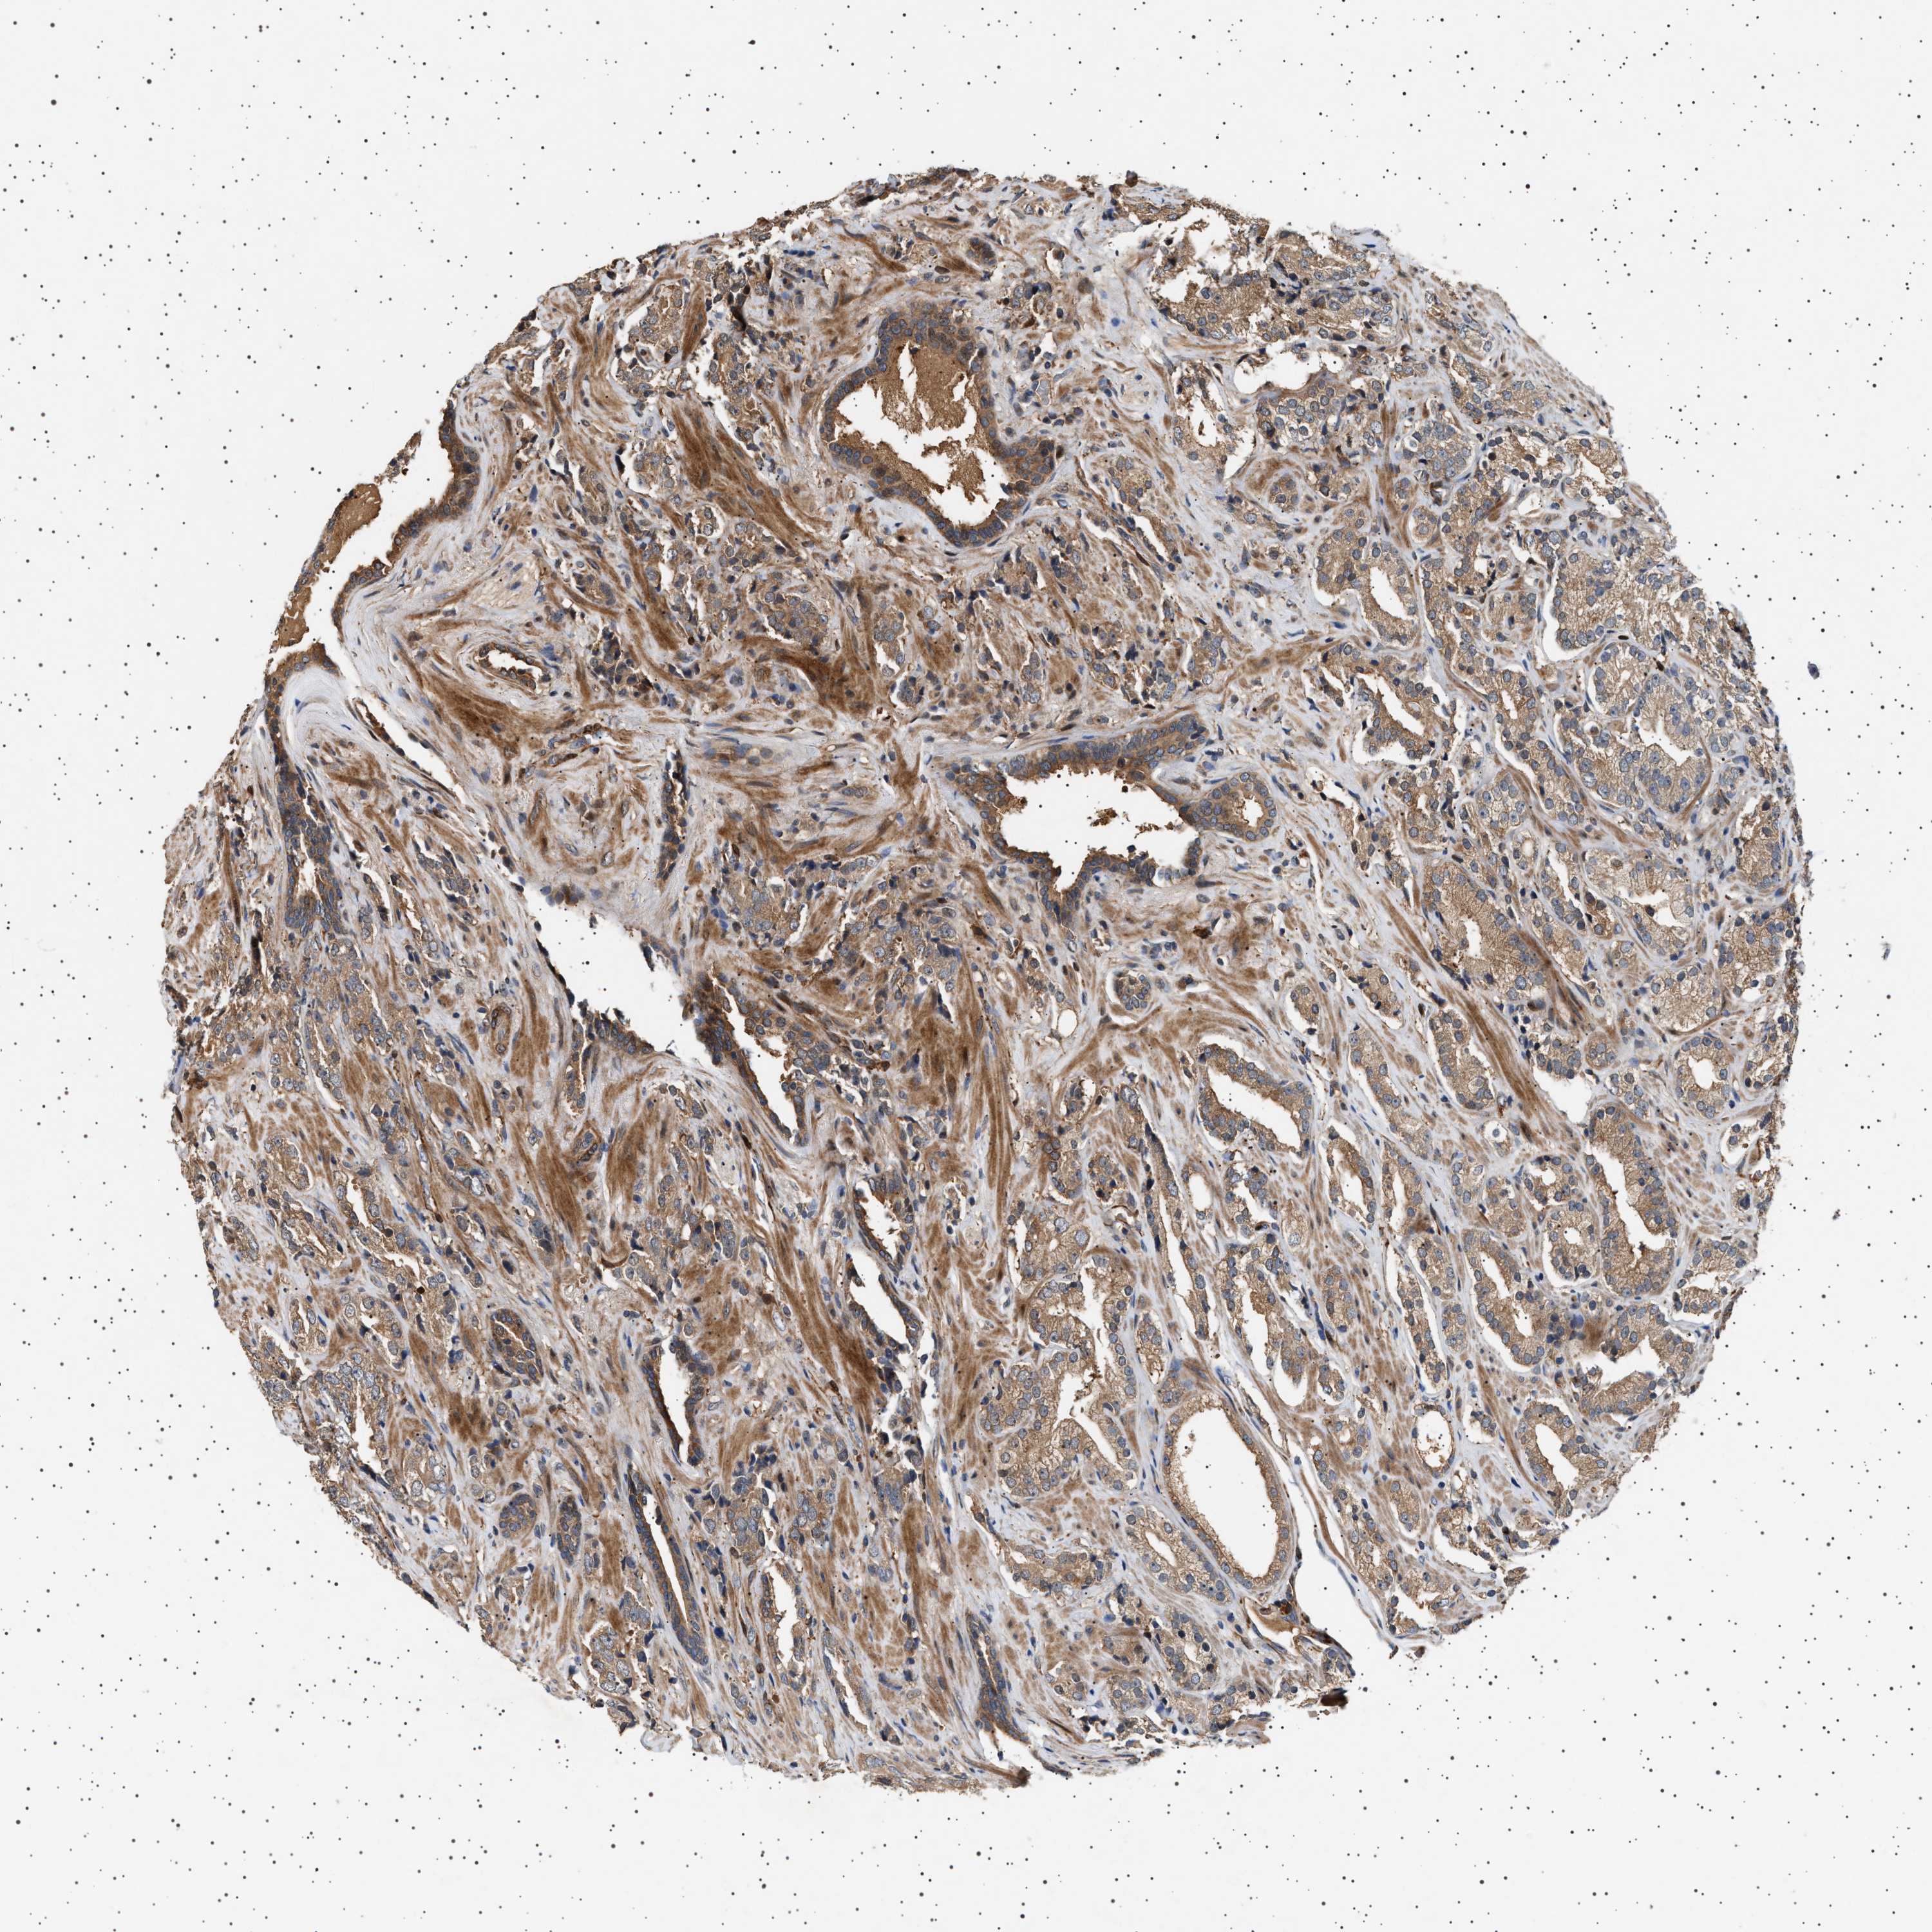

PROSTATE CANCER - Protein expressioni

A mouse-over function shows sample information and annotation data. Click on an image to view it in a full screen mode. Samples can be filtered based on level of antibody staining by selecting one or several of the following categories: high, medium, low and not detected. The assay and annotation is described here.

Antibody stainingi

Antibody staining in the annotated cell types in the current human tissue is reported as not detected, low, medium, or high, based on conventional immunohistochemistry profiling in selected tissues. This score is based on the combination of the staining intensity and fraction of stained cells.

Each image is clickable and will lead to virtual microscopy that enables deeper exploration of all samples and also displays staining intensity scores, fraction scores and subcellular localization as well as patient and tissue information for each sample.

Antibody HPA020870

Antibody CAB010890

Staining

High

Medium

Low

Not detected

Intensity

Strong

Moderate

Weak

Negative

Quantity

>75%

75%-25%

<25%

None

Location

Nuclear

Cytoplasmic/membranous

Cytoplasmic/membranous,nuclear

Adenocarcinoma, High grade

Adenocarcinoma, Low grade